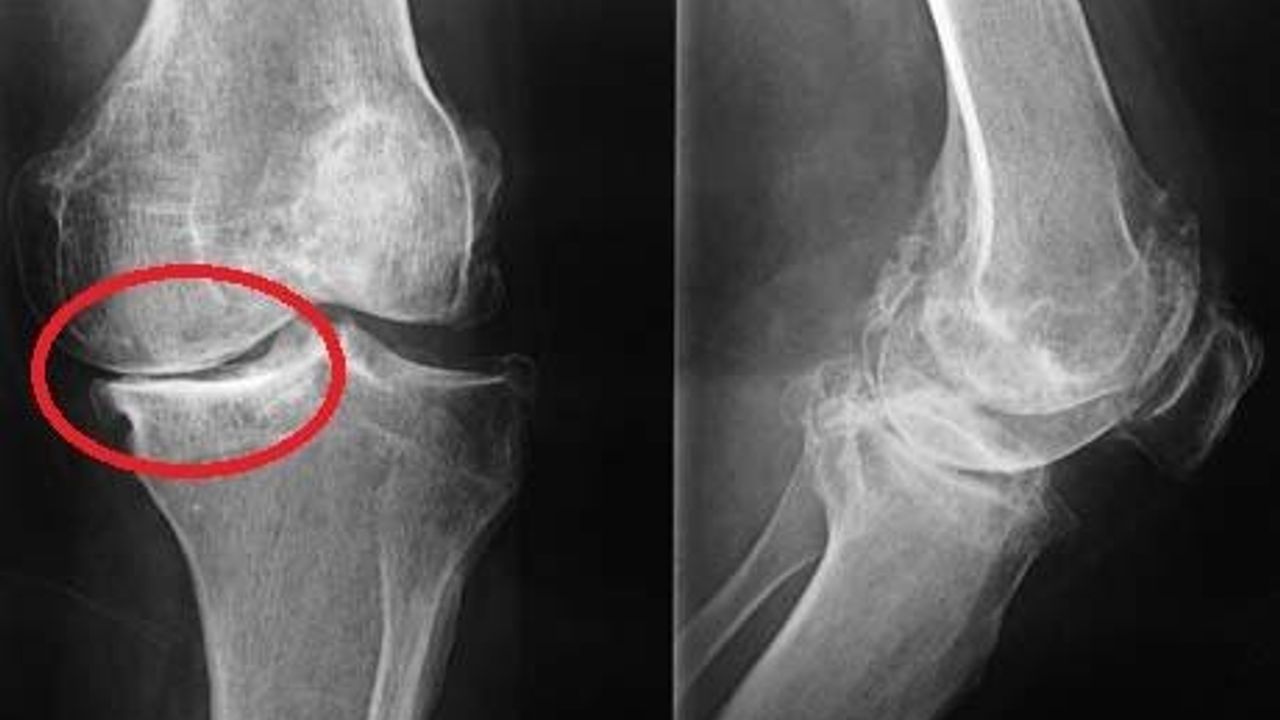

Diz kireçlenmesi (osteoartrit), eklem kıkırdağının zamanla aşınması sonucu ortaya çıkıyor. Uzmanlara göre bu hastalık yalnızca ilerleyen yaşlarda değil; hareketsizlik, fazla kilo ve yanlış spor alışkanlıkları nedeniyle gençlerde de yaygın. Son araştırmalar, diz kireçlenmesinde en iyi sonucun birden fazla yöntemin birlikte uygulanmasıyla elde edildiğini gösteriyor. Uzmanlar bu yaklaşımı üç ana başlıkta özetliyor:

gibi düşük darbeli aktiviteler öneriliyor. Uzmanlar: “Kas güçlü ise kıkırdak daha az aşınıyor.” Günde 20–30 dakika düzenli egzersiz, 6–8 haftada fark yaratabiliyor. ⚖️ Kilo kontrolü eklemi koruyor Vücut ağırlığı dizlere dört kat yük bindiriyor. Bu nedenle 5 kilo zayıflayan bir kişide eklem yükü 20 kilo azalıyor. Kilo vermek, diz ağrısında bilimsel olarak kanıtlanmış bir iyileşme sağlıyor. 💉 Enjeksiyon tedavileri yaygınlaşıyor Ortopedi uzmanlarının en sık kullandığı yöntemler: Hyaluronik Asit Eklem sıvısını artırıyor, sürtünmeyi azaltıyor. Etkisi: 6–12 ay PRP (kendi kanından hazırlanan plazma) Kıkırdak hücrelerini uyarıyor. En iyi sonuç: 👉 PRP + fizik tedavi kombinasyonu Kök hücre Araştırmalar devam ediyor. En çok fayda: 40–60 yaş, orta evre kireçlenmede 💊 İlaçlar kısa süreli destek